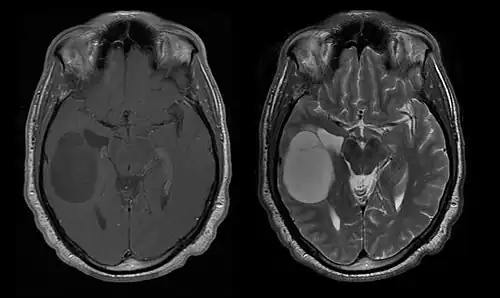

Počítačová tomografie (CT) a magnetická rezonance (MRI) mohou účinně detekovat neoplazii v mozku. MRI je citlivější než CT pro identifikaci lézí, ale má kontraindikace pro pacienty s kardiostimulátory, nekompatibilními protézami, kovovými svorkami a dalšími. CT zůstává metodou volby k detekci kalcifikací v lézích nebo kostních erozích lebky nebo spodiny. Použití kontrastních látek, které jsou v případě CT jodované a v případě MRI paramagnetické ( gadolinium ), umožňuje získat informace o vaskularizaci a integritě hematoencefalické bariéry, lepší definici nádorového nádoru ve srovnání k okolnímu edému a generování hypotéz o stupni malignity. Radiologické vyšetření také umožňuje posouzení mechanických účinků a následných změn v mozkových strukturách vyplývajících z nádoru, jako je hydrocefalus a kýla, jejichž účinky mohou být fatální. Konečně, v rámci přípravy na operaci, může být tato diagnostika použita k určení umístění léze nebo infiltrace nádoru do životně důležitých oblastí mozku. Pro tento účel je MRI účinnější než CT, protože může poskytovat trojrozměrné obrazy.

Diagnostické radiologické zobrazovací nástroje zdůrazňují změnu neoplastické tkáně ve srovnání s normálním mozkovým parenchymem (prostřednictvím změn v elektronicky zobrazené hustotě tkáně na CT a intenzitě signálu na MRI). Jako většina patologických tkání jsou nádory také rozpoznatelné podle zvýšené akumulace intracelulární vody. Na počítačovém tomogramu se jeví hypodenzní, tj. s menší hustotou než mozkový parenchym, na tomogramu nukleární magnetické rezonance s relaxací spin-mřížky hypointenzivní a při spin-spin relaxaci stejně jako protonové vážení (PD) hyperintenzivní.

Počítačová tomografie mozku typicky ukazuje tkáňovou hmotu, která může být zesílena oběma kontrasty. Na CT se gliomy nízkého stupně obvykle jeví jako izodenzní s normálním parenchymem, a proto nemusí vykazovat zvýšení kontrastu. Podobně léze v zadní jámě lebeční, zadní jámě lebeční, je obtížné identifikovat na CT. V důsledku toho výsledky takové tomografie samy o sobě nejsou vždy dostatečné pro diagnostické účely. V pochybných případech je nezbytné použití citlivějšího zobrazování magnetickou rezonancí.

Na -MRI ukazuje intrakraniální tumor jako masivní lézi, která se po použití kontrastní látky může stát více luminiscenční. Vždy však dojde k anomálii signálu -Magnetická rezonance, která indikuje přítomnost neoplazie nebo vazogenního edému. Obvykle zvýšená luminiscence (zesílení kontrastu) svědčí pro nádor vyššího stupně malignity. Pro glioblastom je charakteristický kontrastní prstenec, jehož luminiscenční část odpovídá vitální části maligního nádoru a tmavší -hypointense oblast odpovídající nekróze tkáně.